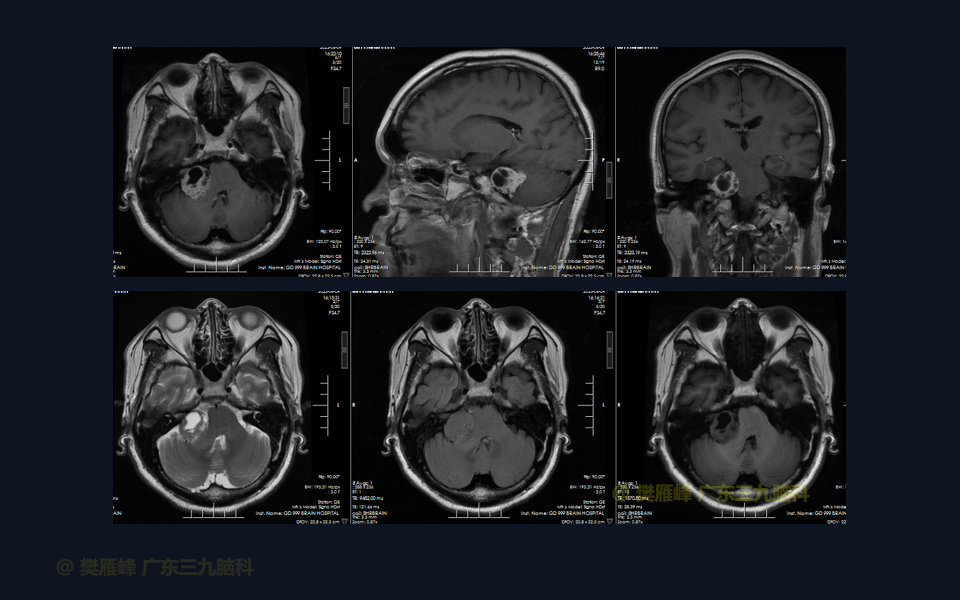

在这个二维手术视频中,展示了一种经枕下乙状窦后入路束膜下分离保留面神经的方法。患者是一名51岁的男性,有1年右耳听力下降伴耳鸣、无步态不平衡病史,术前有右侧轻度面瘫,神经影像学显示右侧桥小脑角区约30×30×29mm的囊实性占位,增强后实性部分及囊壁可见明显强化。他接受了经乙状窦后入路保留面神经的方法,术中肿瘤全切除,面神经被肿瘤挤压成薄膜状覆盖于三叉神经表面。术后面瘫加重,听力未能保留,神经影像学显示肿瘤全部切除。我们展示了安全的颅神经保护和肿瘤切除的细微差别和技术要点,以及手术技术。

在这段手术视频中,展示了一名51岁男性的病例,他因右耳听力下降伴耳鸣1年余发现的右侧听神经瘤。